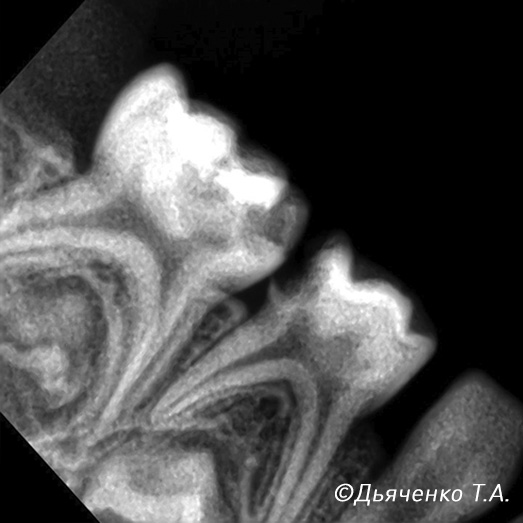

При обратимом процессе удаляется только воспалённая часть нерва (пульпы), а корневая сохраняется (рис. 4 и 5).